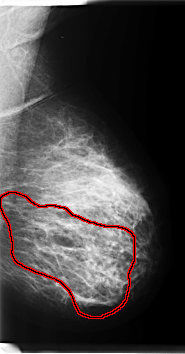

FILE: C_0203_1.LEFT_MLO.OVERLAY

TOTAL_ABNORMALITIES 1

ABNORMALITY 1

LESION_TYPE CALCIFICATION TYPE PLEOMORPHIC DISTRIBUTION REGIONAL

ASSESSMENT 5

SUBTLETY 5

PATHOLOGY MALIGNANT

TOTAL_OUTLINES 1

BOUNDARY